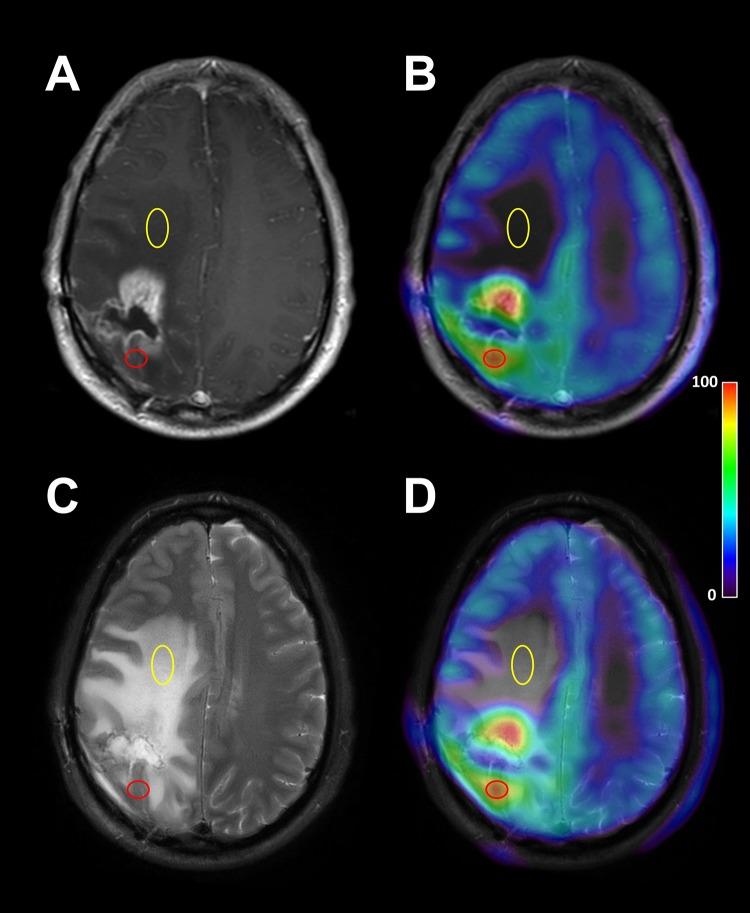

Clinical glioblastoma treatment mostly focuses on the contrast-enhancing tumor mass. Amino acid positron emission tomography (PET) can detect additional, nonenhancing glioblastoma-infiltrated brain regions that are difficult to distinguish on conventional magnetic resonance imaging (MRI). We combined MRI with perfusion imaging and amino acid PET to evaluate such nonenhancing glioblastoma regions.

METHODS

Structural MRI, relative cerebral blood volume (rCBV) maps from perfusion MRI, and α-[C]-methyl-l-tryptophan (AMT)-PET images were analyzed in 20 patients with glioblastoma. The AMT uptake and rCBV (expressed as tumor to normal [T/N] ratios) were compared in nonenhancing tumor portions showing increased signal on T2/fluid-attenuated inversion recovery (T2/FLAIR) images.

RESULTS

Thirteen (65%) tumors showed robust heterogeneity in nonenhancing T2/FLAIR hyperintense areas on AMT-PET, whereas the nonenhancing regions in the remaining 7 cases had homogeneous AMT uptake (low in 6, high in 1). AMT and rCBV T/N ratios showed only a moderate correlation in the nonenhancing regions ( = 0.41, = .017), but regions with very low rCBV (<0.79 T/N ratio) had invariably low AMT uptake.

CONCLUSIONS

The findings demonstrate the metabolic and perfusion heterogeneity of nonenhancing T2/FLAIR hyperintense glioblastoma regions. Amino acid PET imaging of such regions can detect glioma-infiltrated brain for treatment targeting; however, very low rCBV values outside the contrast-enhancing tumor mass make increased AMT uptake in nonenhancing glioblastoma regions unlikely.

临床胶质母细胞瘤治疗大多聚焦于强化的肿瘤块。氨基酸正电子发射断层扫描(PET)能够检测到传统磁共振成像(MRI)上难以区分的额外的、未强化的胶质母细胞瘤浸润脑区。我们将MRI与灌注成像及氨基酸PET相结合,以评估此类未强化的胶质母细胞瘤区域。

方法

对20例胶质母细胞瘤患者的结构MRI、灌注MRI的相对脑血容量(rCBV)图以及α-[C] -甲基-L-色氨酸(AMT)-PET图像进行分析。在T2/液体衰减反转恢复(T2/FLAIR)图像上显示信号增强的未强化肿瘤部分,比较AMT摄取和rCBV(以肿瘤与正常组织的[T/N]比值表示)。

结果

13例(65%)肿瘤在AMT-PET上未强化的T2/FLAIR高信号区域显示出明显的异质性,而其余7例的未强化区域AMT摄取均匀(6例低摄取,1例高摄取)。在未强化区域,AMT和rCBV的T/N比值仅呈中度相关(= 0.41,= 0.017),但rCBV极低(<0.79 T/N比值)的区域AMT摄取始终较低。

结论

这些发现证明了未强化的T2/FLAIR高信号胶质母细胞瘤区域的代谢和灌注异质性。对此类区域进行氨基酸PET成像可检测到胶质瘤浸润的脑区以进行靶向治疗;然而,强化肿瘤块外极低的rCBV值使得未强化的胶质母细胞瘤区域AMT摄取增加的可能性不大。